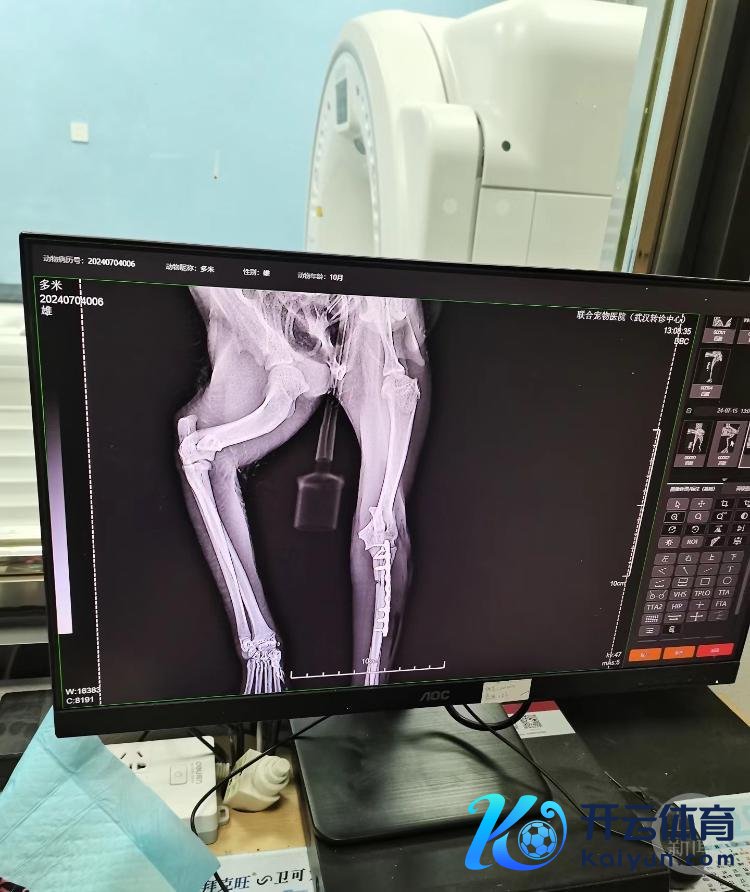

送医后经会诊,多米两条后腿都有伤,一条骨折一条韧带断裂,还追随肺损害等多种症状,情况危险。但运道的是,经两天抢救以及后续的骨折手术和长达半年的康复,在花掉近两万元医疗费后,多米收复了健康。